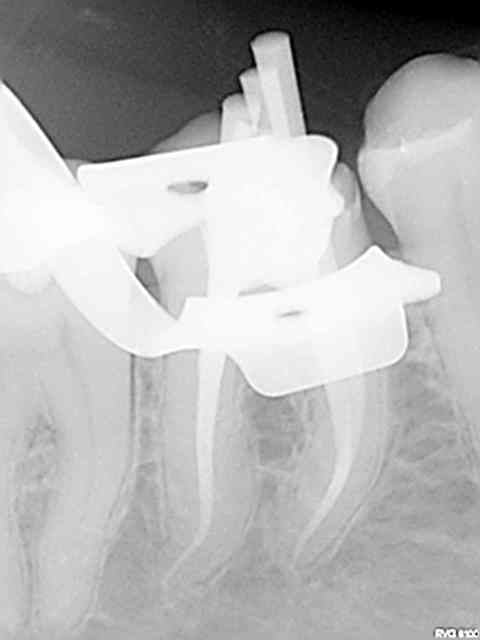

Et une de plus !

R19 vxiysf - Eugenol

R20 kboz6l - Eugenol

01 ukhwbq - Eugenol

C'est pas de la frime hein, mais ca fait plaisir d'avoir trouvé ENFIN une technique rapide et reproductible sans casse. (enfin presque il y a dans le tas un micro morceau de R25 pas loin de l'apex )

Bravo ! Belles images